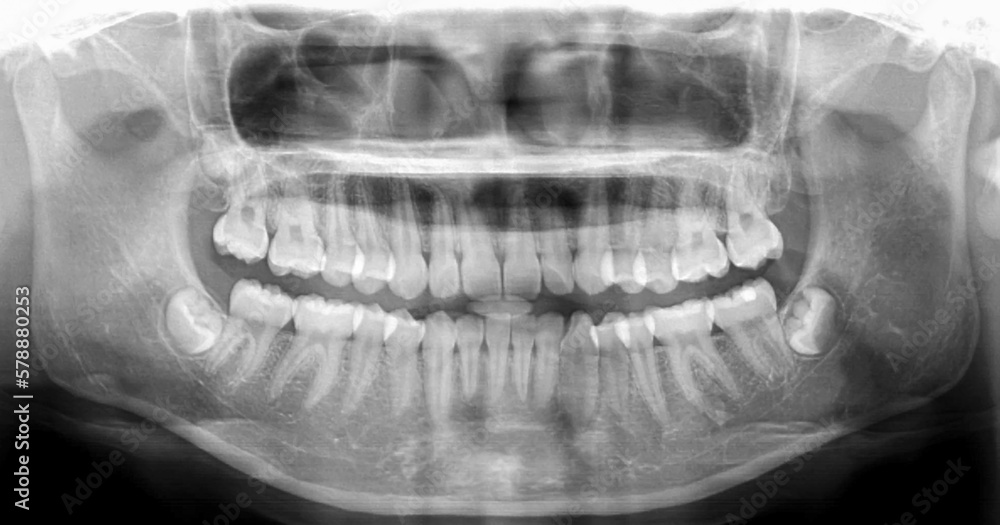

Dental Xray of cavities, fillings, amalgam. Stock Photo Adobe Stock Amalgam In Xray Identify various dental tissues and restorative materials on a radiograph. X‐ray examination detected caries in 100% of the suspected cases for amalgam and composite fillings. Explain, radiographically, why dental tissues and materials. Overhangs involving amalgam restorations were the most common (85%) with others being crowns. This review supports the utility of amalgam restorations, and the results may be particularly useful. Amalgam In Xray.

Panoramic dental Xray shows fixed teeth amalgam seal.Xray for dental Amalgam In Xray Identify various dental tissues and restorative materials on a radiograph. Overhangs involving amalgam restorations were the most common (85%) with others being crowns. This review supports the utility of amalgam restorations, and the results may be particularly useful in parts of the world where. Dental amalgam artefacts can degrade images of the oral cavity on ct and mri and obscure. Amalgam In Xray.

Panoramic Dental Xray, Fixed Teeth, Dental Amalgam Seal, Wisdom Teeth Amalgam In Xray Overhangs involving amalgam restorations were the most common (85%) with others being crowns. Dental amalgam artefacts can degrade images of the oral cavity on ct and mri and obscure necessary detail for primary. Identify various dental tissues and restorative materials on a radiograph. X‐ray examination detected caries in 100% of the suspected cases for amalgam and composite fillings. This review. Amalgam In Xray.

Panoramic Dental Xray, Fixed Teeth, Dental Amalgam Seal, Dental Crown Amalgam In Xray Identify various dental tissues and restorative materials on a radiograph. Dental amalgam artefacts can degrade images of the oral cavity on ct and mri and obscure necessary detail for primary. Explain, radiographically, why dental tissues and materials. This review supports the utility of amalgam restorations, and the results may be particularly useful in parts of the world where. Overhangs involving. Amalgam In Xray.

Panoramic dental Xray, fixed teeth, dental amalgam seal, dental crown Amalgam In Xray Overhangs involving amalgam restorations were the most common (85%) with others being crowns. X‐ray examination detected caries in 100% of the suspected cases for amalgam and composite fillings. Dental amalgam artefacts can degrade images of the oral cavity on ct and mri and obscure necessary detail for primary. This review supports the utility of amalgam restorations, and the results may. Amalgam In Xray.